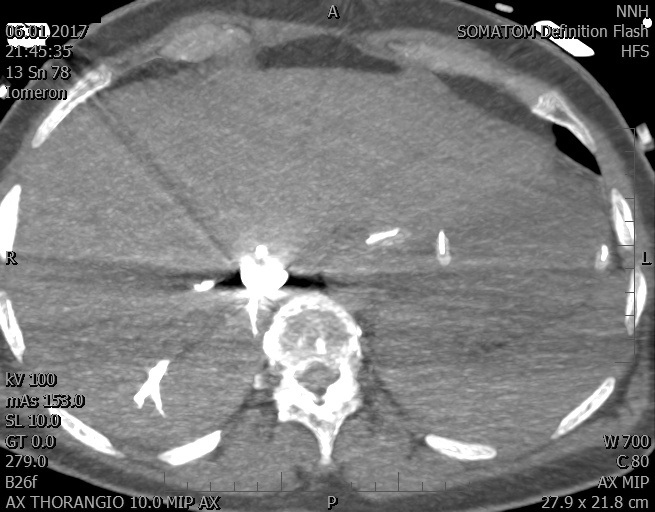

Video 2 - Echokardiograficky byla zjištěna těžká dysfunkce dilatační levé komory s nezvětšenou pravou komorou.Pro nejasnou příčinu zástavy jsme provedli i vyšetření výpočetní tomografií (CT), které vyloučilo plicní embolizaci (série 1 - soubory na konci článku). V den přijetí při přetrvávající oběhové nestabilitě byla nemocná opakovaně defibrilována pro fibrilaci komor se stabilizací rytmu po podání amiodaronu a mesocainu. Dle hemodynamických měření se jednalo o těžký kombinovaný šok. Vstupní laboratorní vyšetření bylo bez větších pozoruhodností. Posléze jsme doplnili anamnézu od příbuzných a zjistili, že pacientka užila do dvou hodin před srdeční zástavou první tabletu amoxicilinu na lehký respirační infekt. Při nevýtěžnosti vstupních vyšetření a nových anamnestických informacích jsme doplnili 14 hodin po kolapsu vyšetření koncentrace tryptázy v séru, která byla extrémně zvýšena (tabulka 2), což nás vedlo k podezření na anafylaxi.